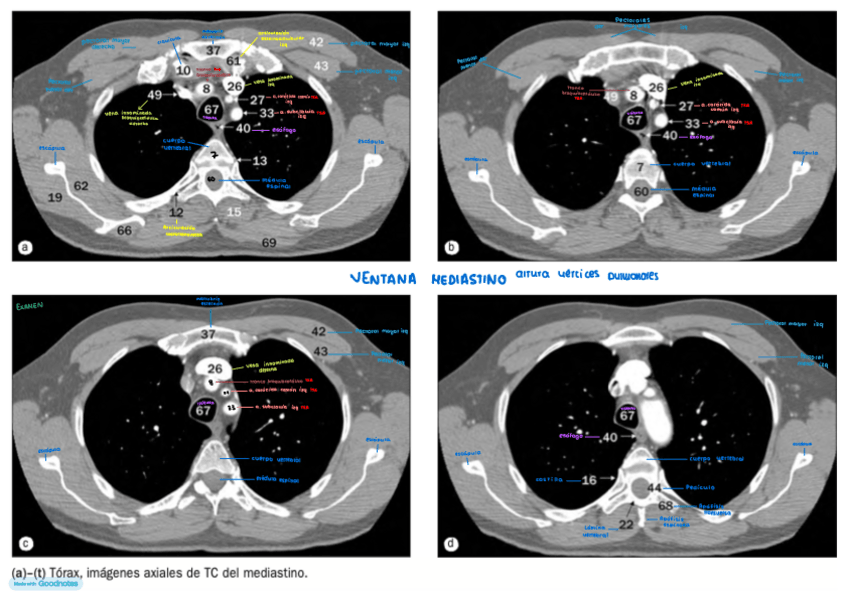

IMAGENES-AXIALES-DE-CUELLO-con-anatomia.pdf

IMAGENES-AXIALES-DE-TORAX-con-anatomia.pdf